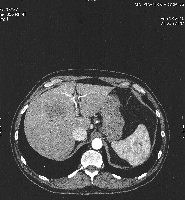

Πρόκειται για άνδρα ασθενή 50 ετών που υποβλήθηκε σε υπέρηχο άνω κοιλίας στα πλαίσια προληπτικού ελέγχου, ο οποίος ανέδειξε ογκόμορφη εξεργασία του ήπατος. Ακολούθησε αξονική τομογραφία, κατά την οποία διαπιστώθηκε μάζα μεγέθους 7 εκατοστών στα ηπατικά τμήματα 4a, 5 και 8 (εικόνα 1) που διηθούσε τη δεξιά και τη μέση ηπατική φλέβα. Επιπλέον, ανιχνεύθηκαν υψηλά επίπεδα α-Fp. Τέθηκε η διάγνωση του ηπατοκυτταρικού καρκινώματος σε έδαφος φυσιολογικού ηπατικού παρεγχύματος. Η ογκομέτρηση των τμημάτων 1, 2 και 3 ανέδειξε προβλεπόμενο σχετικό όγκο ηπατικού υπολείμματος 13,5%. Ο ασθενής υποβλήθηκε σε δεξιό πυλαίο εμβολισμό (εικόνα 2). Τέσσερεις εβδομάδες αργότερα, υποβλήθηκε σε ανάλυση MEVIS, σύμφωνα με την οποία αποφασίστηκε η διενέργεια δεξιάς εκτεταμένης (parenchymal sparing, anterior approach) ηπατεκτομής με προβλεπόμενο σχετικό όγκο ηπατικού υπολείμματος 37,2%. Πέντε εβδομάδες μετά τον πυλαίο εμβολισμό, ο ασθενής υποβλήθηκε στην προαναφερόμενη ηπατεκτομή (εικόνες 4, 5). Έλαβε εξιτήριο την 7η μετεγχειρητική ημέρα. Στην εικόνα 6 παρουσιάζεται το αναγεννώμενο ηπατικό υπόλειμμα, 15 ημέρες μετά την επέμβαση.